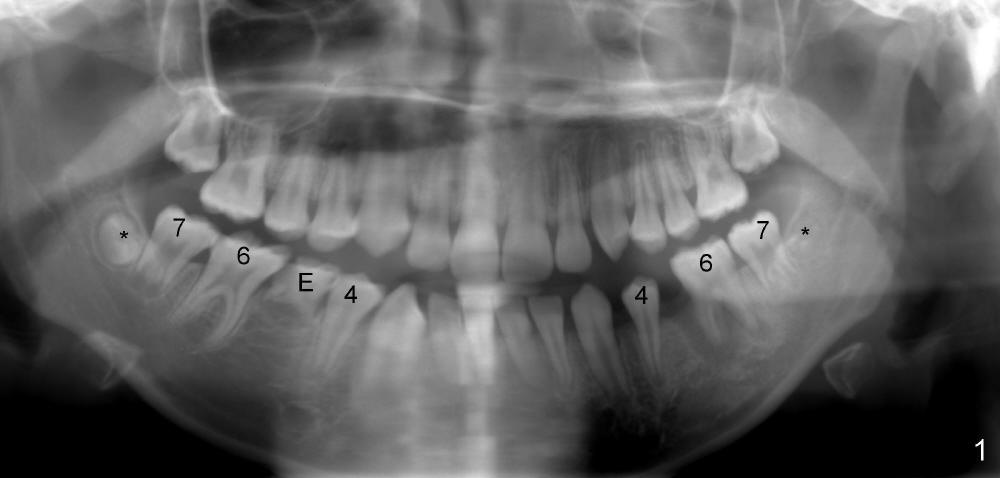

Two lower 2nd bicuspids are congenitally missing in a 11-year-old boy (Fig.1).  The lower left  (LL) E has been extracted due to caries.  There is severe periapical radiolucency associated with the LL6.  Root canal therapy (RCT) is being carried out for this molar with difficulty.  In addition, the boy is a dental phobic, refusing to have the lower right E extracted in spite of DO caries and pain.  In order to reduce the chance of future surgery, including extraction, there are two orthodontic plans to move the lower molars mesially.  Fig.2-4 show that the anterior occlusion and right posterior interdigitation is nearly within normal limit, whereas the left is not.